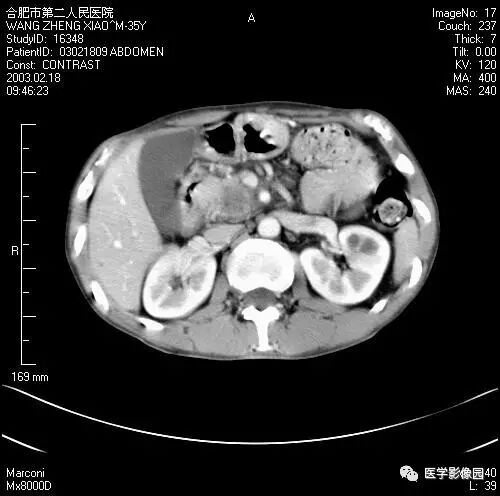

图6-4-13胰腺癌

CT平扫见胰体、尾部局限性肿大,

其内境界不清的低密度灶(↑);

肝右叶有多个低密度转移灶(长↑),

并见腹水